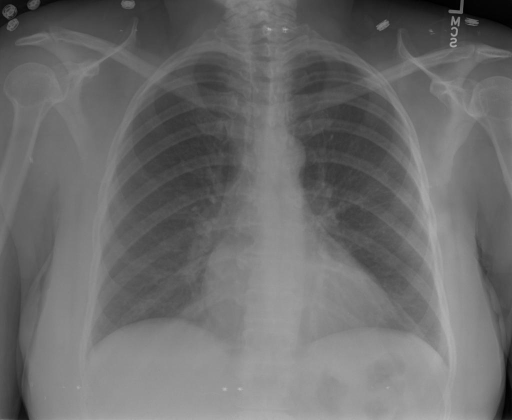

## 本文贡献  - 借助ChatGPT以及公开的数据集,我们构造了一个`X光影像-诊断报告`对的医学多模态数据集; - 我们将构建的中文胸部X光片诊断数据集在[VisualGLM-6B](https://github.com/THUDM/VisualGLM-6B)进行微调训练,并开放了部分训练权重用于学术研究; ## 数据集 - [MIMIC-CXR](https://physionet.org/content/mimic-cxr-jpg/2.0.0/)是一个公开可用的胸部X光片数据集,包括377,110张图像和227,827个相关报告。 - [OpenI](https://openi.nlm.nih.gov/faq#collection)是一个来自印第安纳大学医院的胸部X光片数据集,包括6,459张图像和3,955个报告。 在上述工作中,报告信息都为非结构化的,不利于科学研究。为了生成合理的医学报告,我们对两个数据集进行了预处理,并最终得到了可以用于训练的**英文报告**。除此之外,为了更好的支持中文社区发展,借助ChatGPT的能力,我们将英文报告进行了中文翻译,并最终形成了可用于训练的数据集。 |数据集|数量|下载链接| |:-|:-|:-| |MIMIC-CXR-zh|-|-| |OpenI-zh|6,423|[诊疗报告(英文)](./data/openi-en.json)、[诊疗报告(中文)](./data/Xray/openi-zh.json) 、[X光影像](https://pan.baidu.com/s/13GBsDMKf6xBZBSHpoWH_EA?pwd=k9sh)| ## 快速上手 ### 1.安装环境 ```bash # 安装依赖 pip install -r requirements.txt # 国内换源安装依赖 pip install -i https://mirrors.aliyun.com/pypi/simple/ -r requirements.txt ``` 此时默认会安装`deepspeed`库(支持`sat`库训练),此库对于模型推理并非必要,同时部分`Windows`环境安装此库时会遇到问题。 如果想绕过`deepspeed`安装,我们可以将命令改为: ```bash # 安装依赖 pip install -i https://mirrors.aliyun.com/pypi/simple/ -r requirements_wo_ds.txt # 安装SwissArmyTransformer pip install -i https://mirrors.aliyun.com/pypi/simple/ --no-deps "SwissArmyTransformer>=0.3.6" ``` ### 2.模型推理 |模型权重|下载链接| |:-|:-| |checkpoints-XrayGLM-300|-| |checkpoints-XrayGLM-3000|-| CLI推理: ```python python cli_demo.py --from_pretrained checkpoints/checkpoints-XrayGLM-3000 --prompt_zh '详细描述这张胸部X光片的诊断结果' ``` 更多[参数](https://github.com/WangRongsheng/XrayGLM/blob/main/cli_demo.py#L16) ### 3.模型训练(复现XrayGLM) > 我们所使用的硬件为:四卡A100 80GB - (1)准备[诊疗报告(中文)](./data/Xray/openi-zh.json)和[X光影像](https://pan.baidu.com/s/13GBsDMKf6xBZBSHpoWH_EA?pwd=k9sh)在`data/Xray`文件夹下; - (2)开始训练: ```bash # 设置CUDA变量,主要是为了解决有时候直接训练而出现无法正确加载到显卡问题 export CUDA_VISIBLE_DEVICES=0,1,2,3 # 开始训练 bash finetune_XrayGLM.sh ``` 这里的复现过程非常简单,主要是很多过程我们都为大家准备好了,大家可以随时复现一个自己的`XrayGLM`。 ### 4.模型训练(通用) ## 效果展示 影像诊断: |X光影像|诊疗报告(医生)|XrayGLM| |:-|:-|:-| ||根据X射线图像,心脏大小正常,肺部看起来很清晰。已经排除了肺炎、积液、水肿、气胸、腺病、结节或肿块的存在。该发现表明一切正常。换句话说,总体印象是胸部正常。|X光片显示,心脏大小正常。肺部没有气胸或胸腔积液的证据。骨骼结构看起来没有任何异常。总的来说,X光片表明没有发现急性心肺疾病的迹象。| ||X光图片显示没有扭曲的区域、可疑的骨质不透明度或胸腺积液。心脏大小轻微增大,但非常稳定。此外,没有气胸的证据,肺野也正常。总体来说,X光片显示没有急性心脏异常,但要注意轻微的心脏扩大。|X光片显示,心脏大小正常。肺部和纵隔轮廓清晰,没有气胸或胸腔积液的证据。骨骼结构完整,没有任何急性异常。| ||心影形态在正常范围内。没有急性骨质异常。有可能出现没有明显的吸水或肺实质状况的线索。没有大面积积液或气胸。有可能怀疑其有误吸或肺实质问题。为了确诊和治疗,可能需要进行适当的影像学随访。|心脏大小正常,肺部和纵隔轮廓清晰。没有急性异常或活动受限的证据。没有任何明显的气胸、胸腔积液或肺不张的迹象。此外,也没有发现任何局灶性骨质异常或其他急性疾病。| 多轮对话: |X光影像|诊疗报告(医生)| |:-|:-| ||右侧主动脉突出观察到。心脏大小正常。胸部未发现明显的肺气肿、胸膜积液或可疑的肺部病变。报告指出已知右侧主动脉情况正常。| ```bash >> X光影像路径:./data/Xray/861_1.png >> 用户:这是一张什么图? >> XrayGLM:这张图片显示的是一张肺部检查的X光片。 >> 用户:请描述这张胸部X光片的诊断结果 >> XrayGLM:心脏大小正常,肺部清晰。没有急性心肺疾病的证据。 >> 用户:是否存在肺气肿? >> XrayGLM:没有肺气肿。心脏大小正常,肺部清晰。没有发现急性心肺疾病的证据。 >> 用户:平时饮食该注意什么? >> XrayGLM:饮食应该健康,均衡。建议增加蛋白质的摄入量,因为蛋白质有助于维持肌肉和骨骼的健康。多食用蔬菜、水果、全谷物以及健康的脂肪来源如橄榄油、鱼类等可以帮助获得足够的维生素和矿物质。此外,避免过度饮酒或吸烟,这些习惯可能会对心脏健康产生负面影响。 ``` ## 未来展望 1. 模型的能力更多来源于数据的支持,`OpenI-zh`作为微调数据集,其数据量足以支持研究,在更广泛的任务和性能表现上,我们认为**在大规模数据集上预训练并在高质量少量数据集上微调是一种可行的方案**; 2. 普遍意义的理解上,视觉多模态模型=视觉模型+语言模型。除了需要关注视觉模型信息与语言模型输出的搭配外,还需要**额外关注到语言模型的加强,在人机的对话中,尤其是医疗语言模型的问答上,除了专业的医疗问题回答,带有人文情怀的有温度的回答更应该是我们追寻的目标**。 ## 项目致谢 1. [VisualGLM-6B](https://github.com/THUDM/VisualGLM-6B)为我们提供了基础的代码参考和实现; 2. [MiniGPT-4](https://github.com/Vision-CAIR/MiniGPT-4)为我们这个项目提供了研发思路; 3. ChatGPT生成了高质量的中文版X光检查报告以支持XrayGLM训练; 4. [gpt_academic](https://github.com/binary-husky/gpt_academic)为文档翻译提供了多线程加速; 5. [MedCLIP](https://github.com/RyanWangZf/MedCLIP) 、[BLIP2](https://huggingface.co/docs/transformers/main/model_doc/blip-2) 、[XrayGPT](https://github.com/mbzuai-oryx/XrayGPT) 等工作也有重大的参考意义;  这项工作由[澳门理工大学应用科学学院](https://www.mpu.edu.mo/esca/zh/index.php)硕士生[王荣胜](https://github.com/WangRongsheng) 、[段耀菲](https://github.com/IsBaSO4) 、[李俊蓉](https://github.com/lijunrong0815)完成,指导老师为檀韬副教授、[彭祥佑](http://www.patrickpang.net/)老师。 *特别鸣谢:[USTC-PhD Yongle Luo](https://github.com/kaixindelele) 提供了有3000美金的OpenAI账号,帮助我们完成大量的X光报告翻译工作 ## 免责声明 本项目相关资源仅供学术研究之用,严禁用于商业用途。使用涉及第三方代码的部分时,请严格遵循相应的开源协议。模型生成的内容受模型计算、随机性和量化精度损失等因素影响,本项目无法对其准确性作出保证。即使本项目模型输出符合医学事实,也不能被用作实际医学诊断的依据。对于模型输出的任何内容,本项目不承担任何法律责任,亦不对因使用相关资源和输出结果而可能产生的任何损失承担责任。 ## 项目引用 如果你使用了本项目的模型,数据或者代码,请声明引用: ```bash @misc{wang2023XrayGLM, title={XrayGLM: The first Chinese Medical Multimodal Model that Chest Radiographs Summarization}, author={Rongsheng Wang, Yaofei Duan, Junrong Li, Patrick Pang and Tao Tan}, year={2023}, publisher = {GitHub}, journal = {GitHub repository}, howpublished = {\url{https://github.com/WangRongsheng/XrayGLM}}, } ``` ## 使用许可 此存储库遵循[CC BY-NC-SA](https://creativecommons.org/licenses/by-nc-sa/4.0/) ,请参阅许可条款。